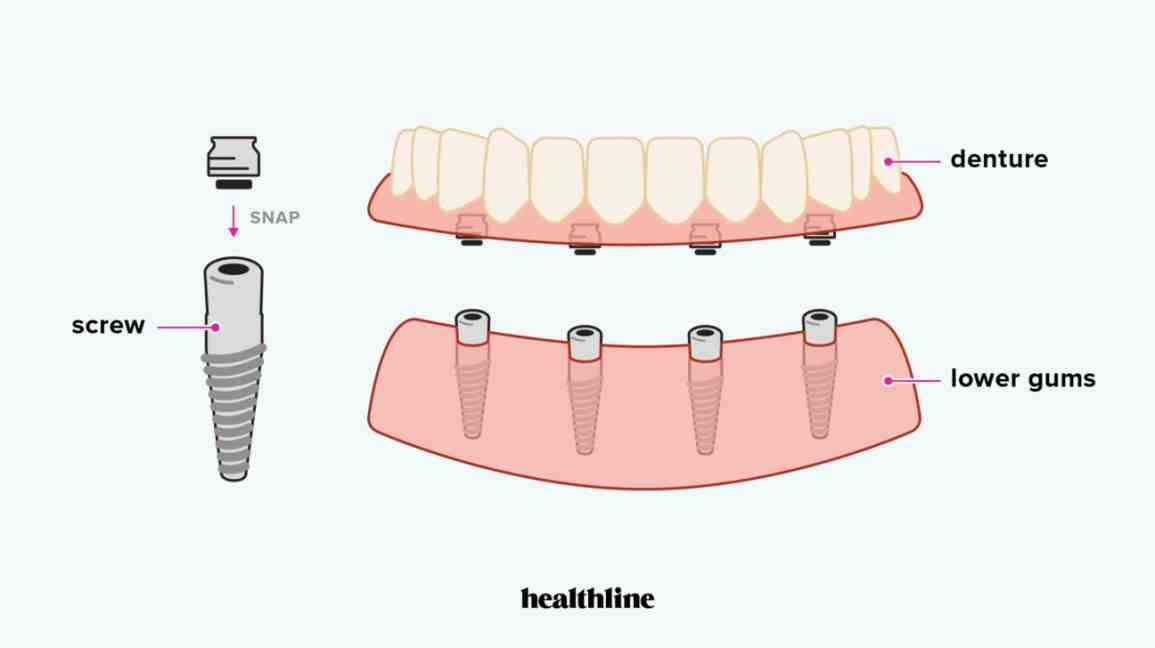

Full oral treatment usually consists of: The placement of six to eight dental implants in the upper jaw. Four to six implants in lower jaw.